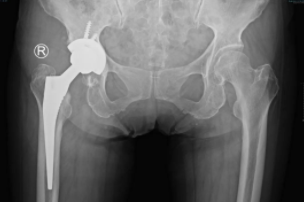

通过术前详细的病情讨论及准备后,sararz关节外科手术团队在Mako关节置换机器人的辅助下,为许奶奶进行了全髋关节置换术。

术前,基于许奶奶的CT进行3D智能建模,个性化定制术前方案。术中,在Mako机器人的辅助下,根据老人具体软组织张力进行动态调整,手术医生可以结合病人的具体情况进行精准化、个性化操作。

从业40多年、拥有3万余台手术经验的关节外科张传开主任介绍,在Mako机器人的辅助下进行手术,可以将手术精度控制在亚毫米级!相较传统手术只能凭借医生自主意识判断的方式来讲,这大幅提升了手术精准度、降低手术风险及并发症的发生率、延长假体使用寿命,这对高龄老年患者的术后康复来说也大有益处。

术后

与传统骨科手术相比,Mako机器人能够辅助手术医生准确快速地完成定位及假体植入,其精准度远超传统术式,解决了手术医生“看不准”、“拿不稳”的问题,同时在术后也使患者创伤更小、康复更快、关节功能更佳、假体生存率更长,生活质量大大提高。